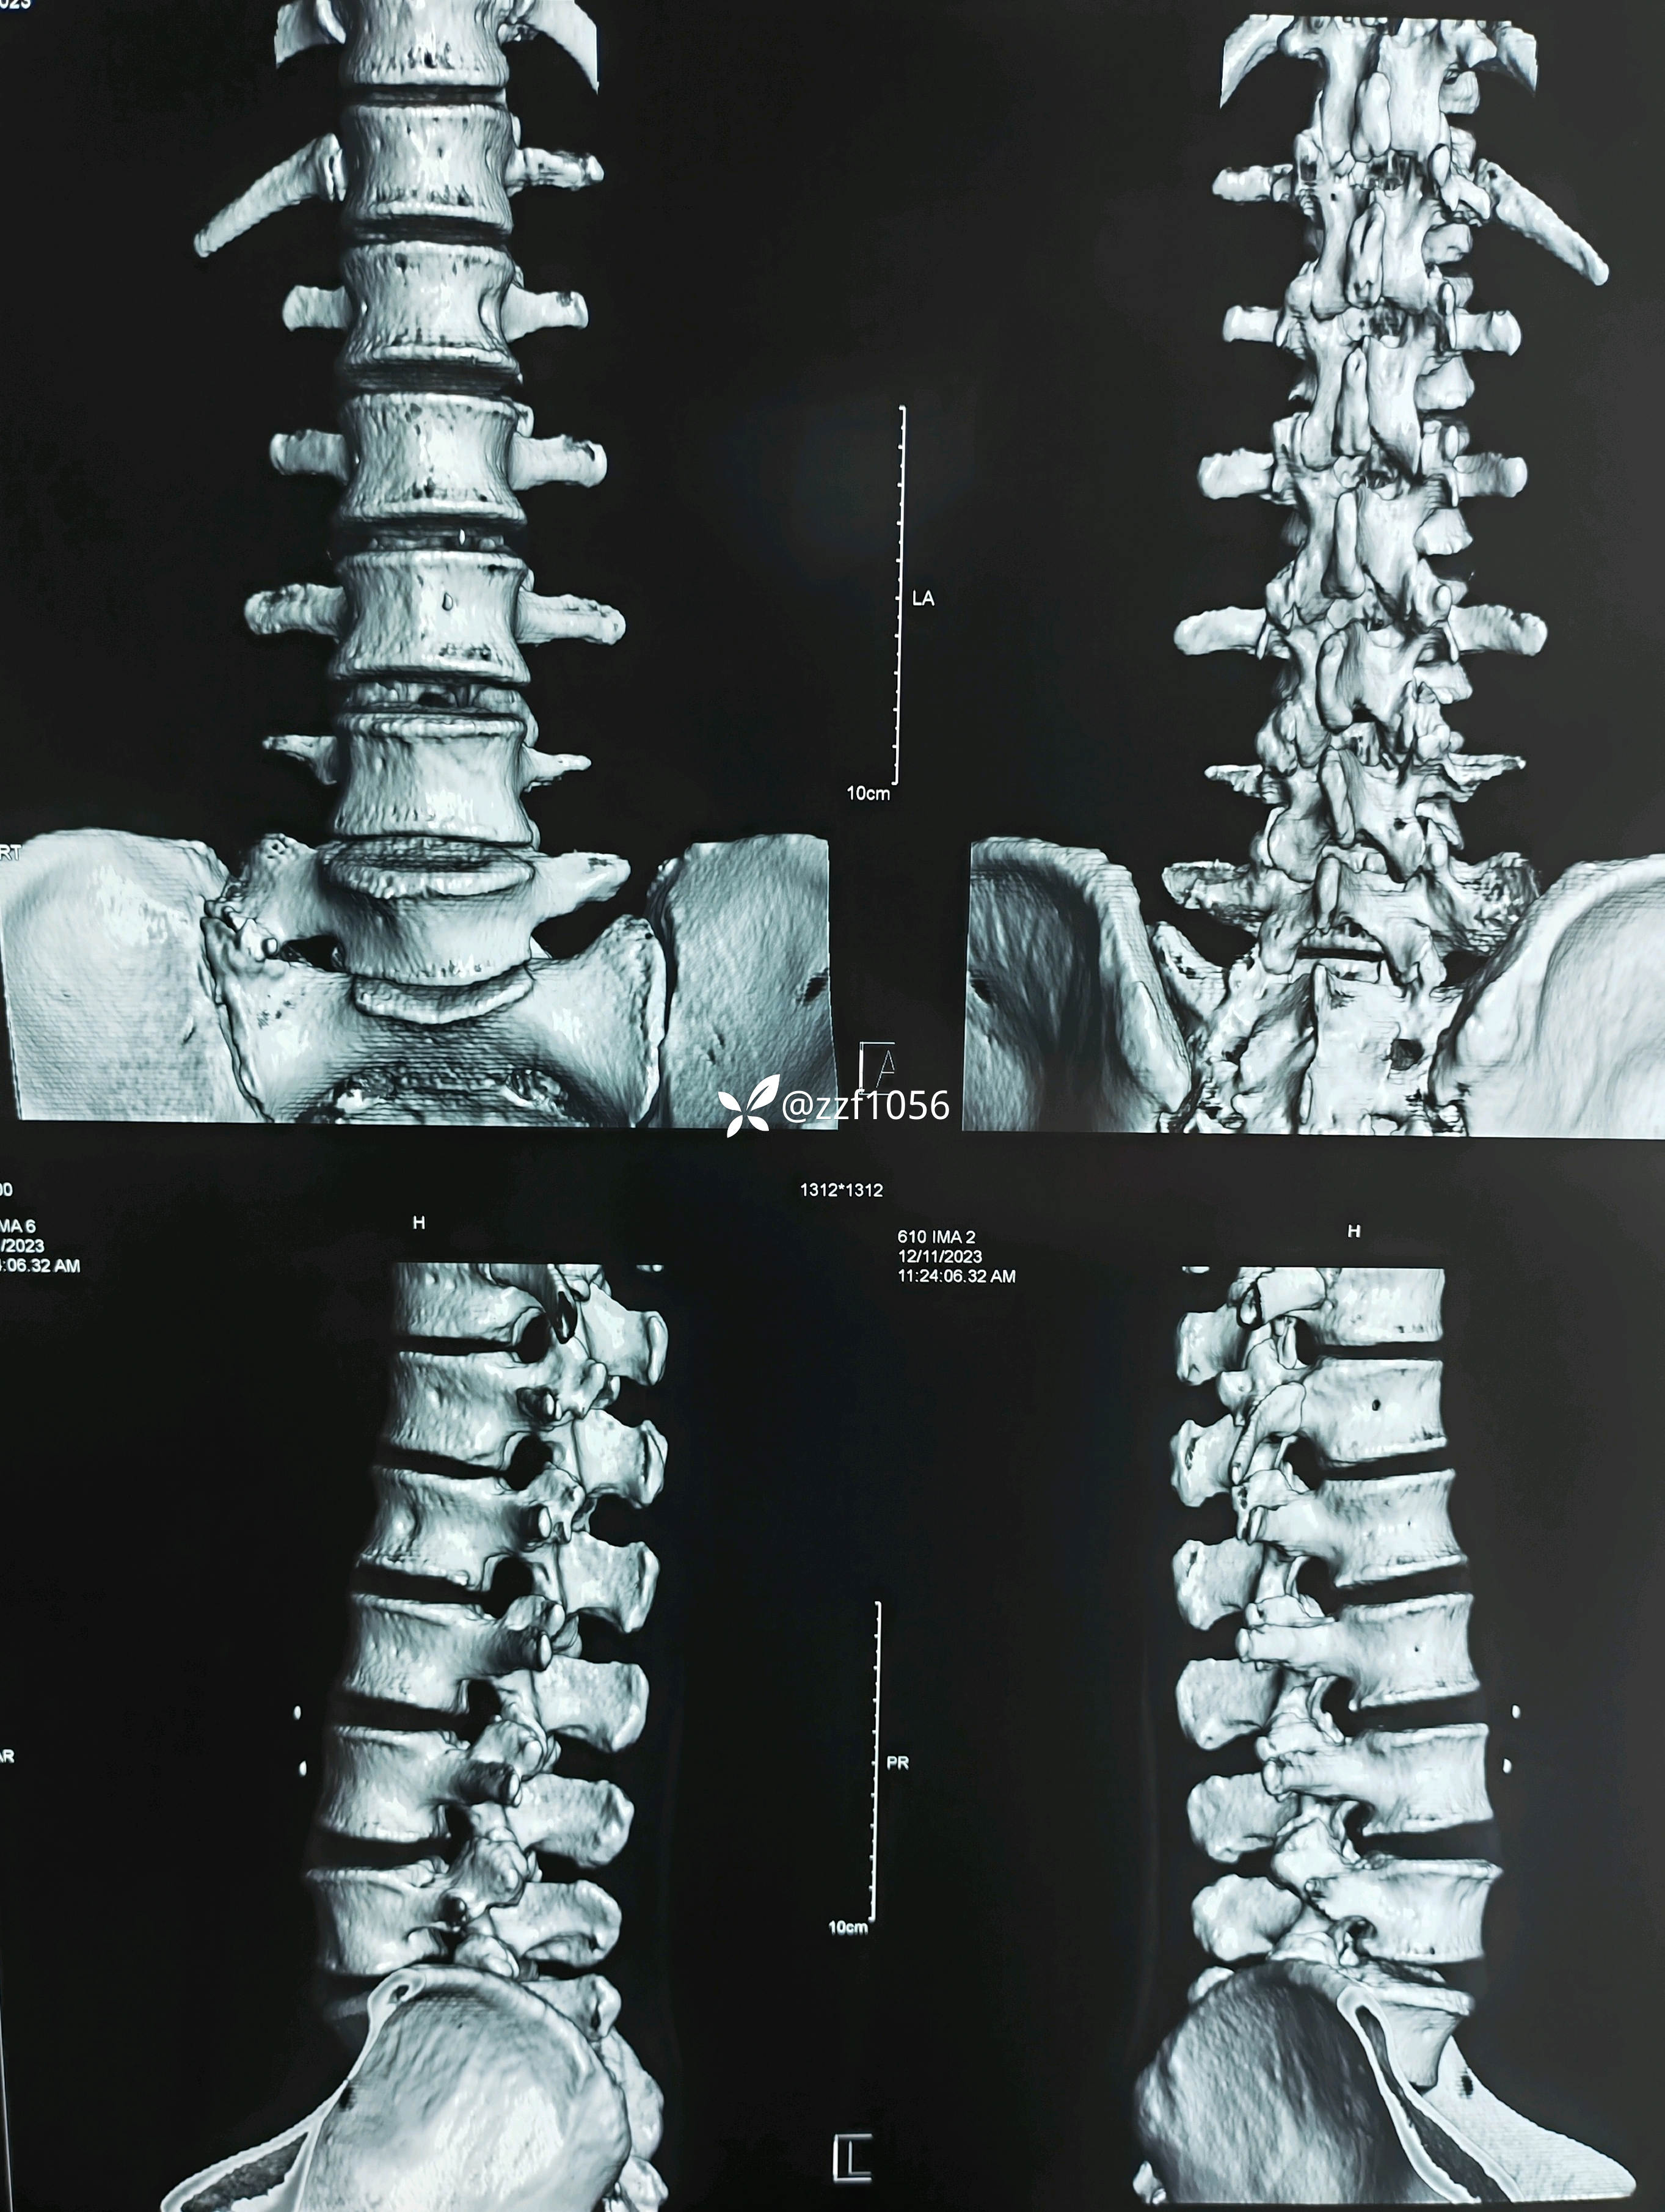

入院诊断:腰椎间盘突出症伴神经根病(L4/5)

L4/5相对好穿刺